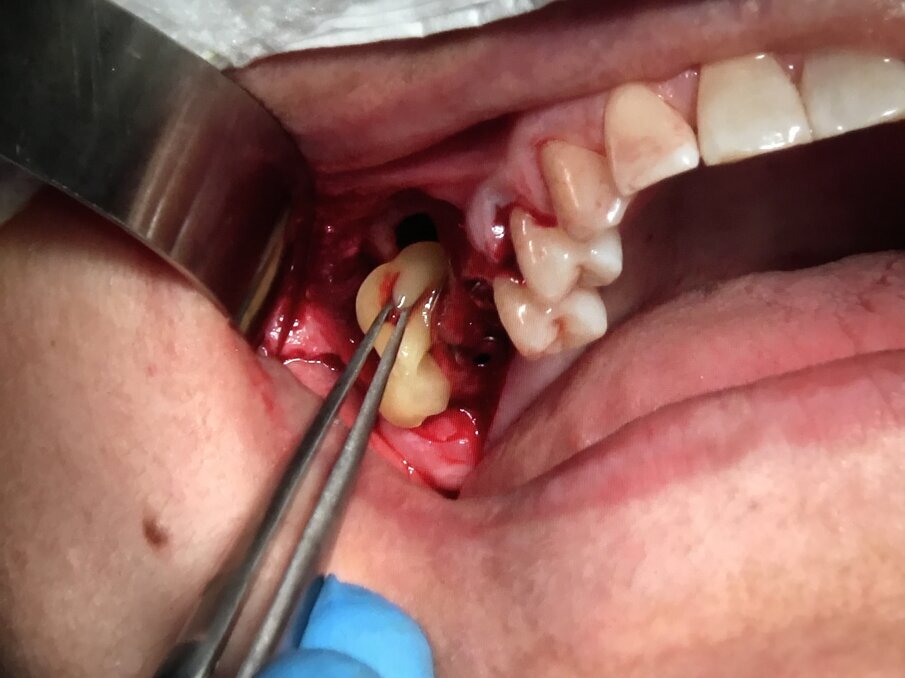

Infatti l’azione combinata su tessuti molli e su quelli duri, favorisce la rapida guarigione degli interventi chirurgici parodontali e delle tecniche additive ossee. Queste ultime devono essere predicibili, efficaci, sicure e poco costose soprattutto in relazione al fatto che tali tecniche spesso, sono finalizzate alla riabilitazione implantare e protesica delle arcate dentarie. In tal senso una tecnica che rende rapido e sicuro un ciclo riabilitativo implantoprotesico, diventa necessariamente una strategia terapeutica vincente. Diverse aziende implantari hanno sviluppato conoscenze scientifiche ed abilità commerciali in questo settore; a seguire la documentazione iconografica di una sequenza chirurgica in cui l’inserzione implantare e la rigenerazione ossea guidata sono supportate da I-PRF, utilizzato come carrier addizionato a xenoinnesti di origine bovina e da A-PRF, utilizzato come bio-membrana; quest’ultimo per proteggere impianti inseriti ed innesti anziché i tradizionali lembi muco-periosti di scorrimento affrontati e suturati tra di loro (Figg. 11-15).

Fig. 11 - Fase 1: siti estrattivi preparati in modo traumatico con Courretage.

Fig. 12 - Fase 2: Impianti Multysystem inseriti e filino della discrepanza alveolo-implantare con I-PRF addizionato di xenoinnesto.